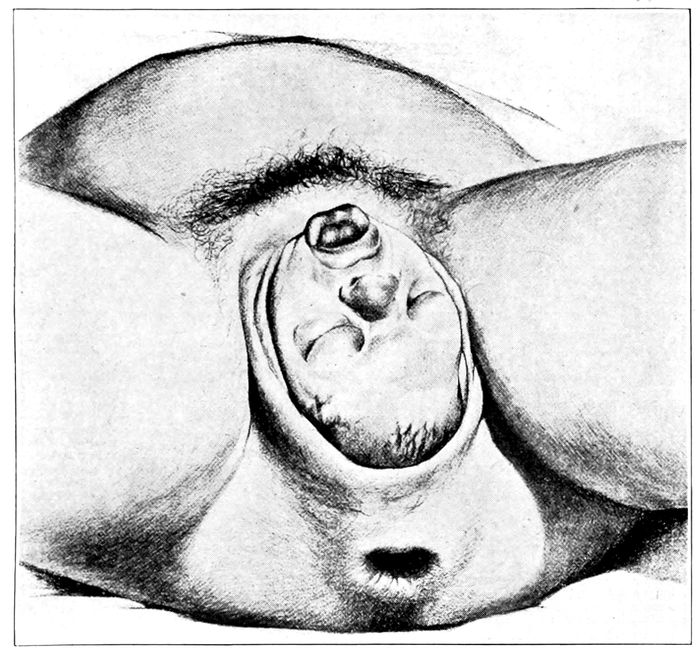

Face presentation |

175 |